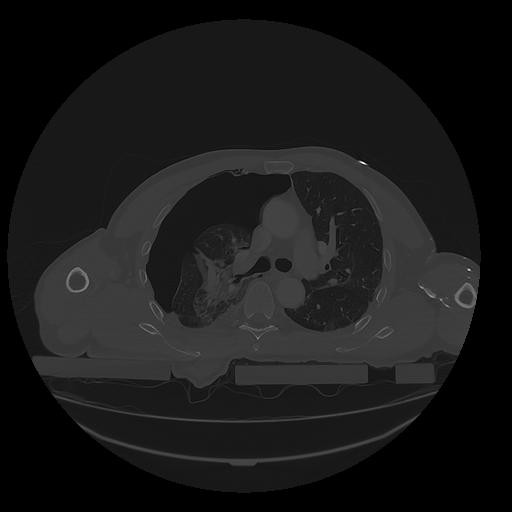

31 PULMON,CE,Vol,1.0,PULMON,,